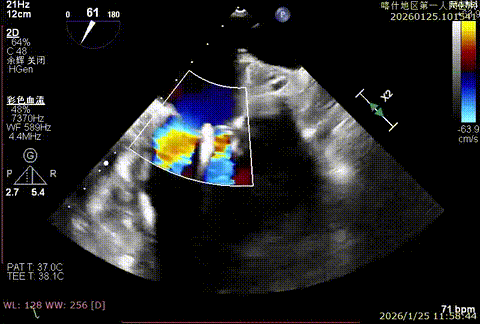

该例患者为VFMR,术前制定手术策略:患者二尖瓣重度反流,后叶严重栓系,心房心室扩大。患者瓣口面积4.5cm2,预计使用两枚XTR解决患者瓣叶脱垂和反流。考虑到先于2区进行钳夹,应该能获得足够的房间隔穿刺高度。术中经不断调整穿刺位点,最终穿刺高度4.4cm。成功穿刺后将第一枚XTR送入二尖瓣正上方,进行弹道测试Orientation调整后,最终定位于2区正上方下左心室。第一枚夹子在左室成功捕捞和钳夹瓣叶后,瓣叶反流程度显著降低,夹子外侧仍见部分反流,随后在第一枚夹子外侧再次放置一枚XTR,瓣叶反流程度进一步降低至微量。通过TEE观察,二尖瓣双孔组织桥稳定,跨瓣压差3mmHg,肺静脉逆流改善明显,手术安全结束。

反流充分降低

术后压差3mmHg